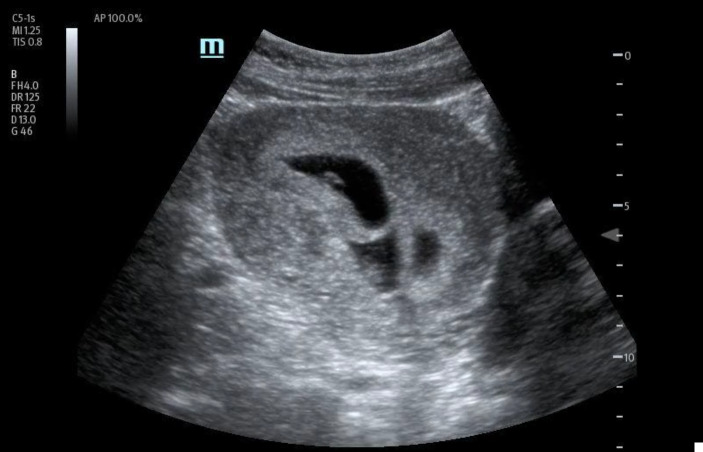

处理多胎妊娠具有挑战性,需要仔细评估。护理点超声检查(POCUS)已成为评估疑似头胎妊娠的潜在重要工具。然而,它在评估多胎妊娠中的作用仍不确定。我们介绍了一例 36 岁加纳女性的病例,她在接受体外受精后出现急性阴道出血。床旁经腹 POCUS 检查发现有四个宫内妊娠,胎儿有胎儿极和心脏活动,提示为四胞胎可存活妊娠。随后的经阴道超声检查证实了这一结果。患者出院后与妇产科医生进行了复诊。本病例强调了 POCUS 在早孕诊断中的重要性,有助于准确识别和适当转诊,以便进一步处理。它还证明了 POCUS 在确定孕龄和胎儿存活率方面的实用性。据我们所知,目前还没有发表过专门针对四胞胎妊娠诊断的病例报告,这强调了 POCUS 在优化高危多胎妊娠护理中的作用。

Managing multiple pregnancies is challenging and requires careful evaluation. Point of care ultrasound (POCUS) has emerged as a potentially crucial tool in assessing suspected first-trimester pregnancies. However, its role in evaluating multiple pregnancies remains uncertain. We present the case of a 36-year-old Ghanaian female who presented with acute vaginal bleeding after undergoing in vitro fertilization. A bedside transabdominal POCUS identified four intrauterine gestations with fetal poles and cardiac activity, suggesting a quadruplet viable pregnancy. A subsequent transvaginal ultrasound confirmed the findings. The patient was discharged with a follow-up appointment with an Obstetrician-Gynecologist. This case highlights the significance of POCUS in early pregnancy diagnosis, facilitating accurate identification and appropriate referral for further management. It also demonstrates the utility of POCUS in determining gestational age and viability. To our knowledge, no published case reports specifically address the diagnosis of a quadruplet pregnancy, emphasizing the role of POCUS in optimizing care for high-risk multiple pregnancies.